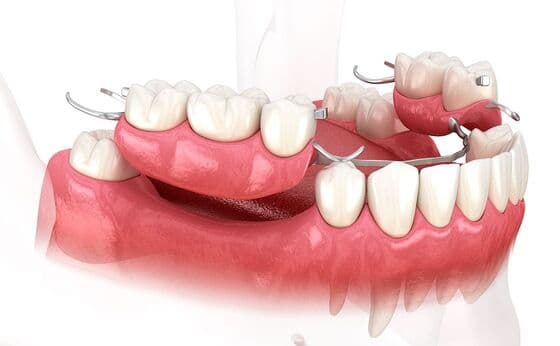

Denture treatment

入れ歯治療

入れ歯は、歯を失った部分を補う取り外し可能な人工の歯です。部分入れ歯と総入れ歯があり、手軽に咀嚼機能を回復できます。外科手術が不要ですが、噛む力が天然歯より劣り、装着時の違和感が生じることもあります。

入れ歯治療について

入れ歯の噛む力は天然歯やインプラントに比べると、10%~40%と言われており、入れ歯が大きくなるほど咀嚼能力は低下します。しかし、入れ歯治療はインプラントのような異物を体内に入れたり、ブリッジのように歯を削ったりしないので、歯を失った時の治療では生体への侵襲は一番低い治療になります。